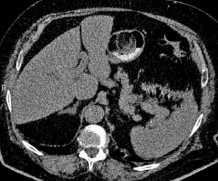

Ruột non: Tác giả Mohammad Amx (Mỹ) là người đầu tiên thông báo trường hợp u mỡ ác tính của ruột non (1957), khối u này gây tắc ruột do lồng ruột non trên một đoạn 15 cm [95], đây là một trong những biến chứng do u gây ra như tắc ruột, xoắn ruột, chảy máu [84, 96]. Một trong những biến chứng hiếm gặp khác mà tác giả Hasashi (Nhật Bản) và cộng sự đã mô tả là thủng ruột gây viêm phúc mạc do u mỡ ác tính gây ra, đây là một trong hai trường hợp trong y văn mà chúng tôi tìm thấy cùng với bài viết của tác giả người Ba Lan đăng năm 1984 [97]. Chẩn đoán trước mổ bằng lâm sàng thường khó khăn, nhờ có chụp cắt lớp hoặc viên camera nội soi mới cho gợi ý chẩn đoán [98].

Hình 1.15. U mỡ ác tính ruột non, ảnh chụp từ viên camera nội soi [98]